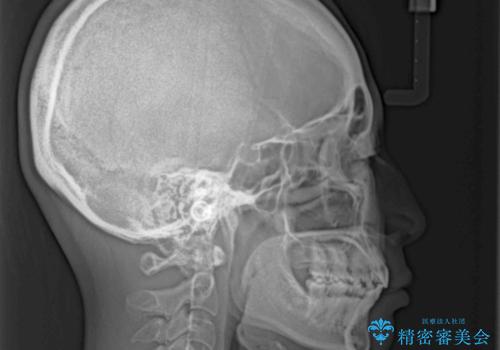

強い咬合力により前歯の隙間がなかなか閉じられず、治療期間は長いものとなりましたが、横顔の印象が大きく変わるほど口元の印象を改善することができました。